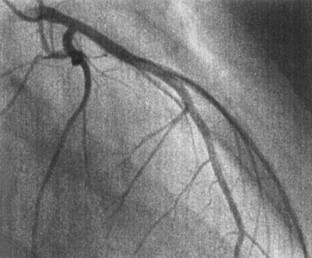

We report two young adult patients who had acute coronary syndrome after regression of coronary aneurysms caused by Kawasaki disease (KD). A 26 year-old man had acute anterior myocardial infarction at midnight after drinking alcohol. He had had bilateral coronary aneurysms caused by KD at the age of 8 months. Selective coronary angiograms (CAGs) at the age of 7 years revealed regression of both coronary aneurysms. He had no symptoms until the onset of acute myocardial infarction. The other patient was a 24 year-old man diagnosed as having a subendocardial infarction. He had had bilateral coronary aneurysms caused by KD at the age of 1 year. CAGs at the age of 9 years showed that both had regressed. It should be recognized that young adults with apparently normal coronary arteries angiographically after regression of large coronary aneurysms caused by KD may occasionally have acute coronary syndromes. We suspect intimal involvement of the coronary arterial wall after regression of the large aneurysms underlies the acute coronary syndrome in adults. Risk factors for atherosclerosis must be avoided in this population.

Fig. 2